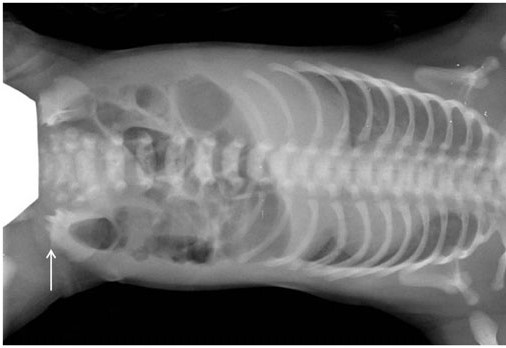

Jeuneov syndróm (asfyktizujúca dysplázia hrudníka, anglicky Jeune syndrome, asphyxiating thoracic dystrophy) je geneticky podmienený syndróm krátkych rebier. Hlavným prejavom je deformácia hrudného koša, čo vedie k poruche vývoja pľúc, dychovéj tiesni až k smrti. Ďalej sú postihnuté končatiny a obličky.

Deformity hrudníka možno pozorovať už v tehotenstve pomocou ultrazvuku, k určeniu diagnózy vedú typické prejavy, postihnutie kostí sa dá zobraziť pomocou RTG, CT alebo MR, možné je tiež genetické testovanie.

• deformity hrudníka - tvar zvona